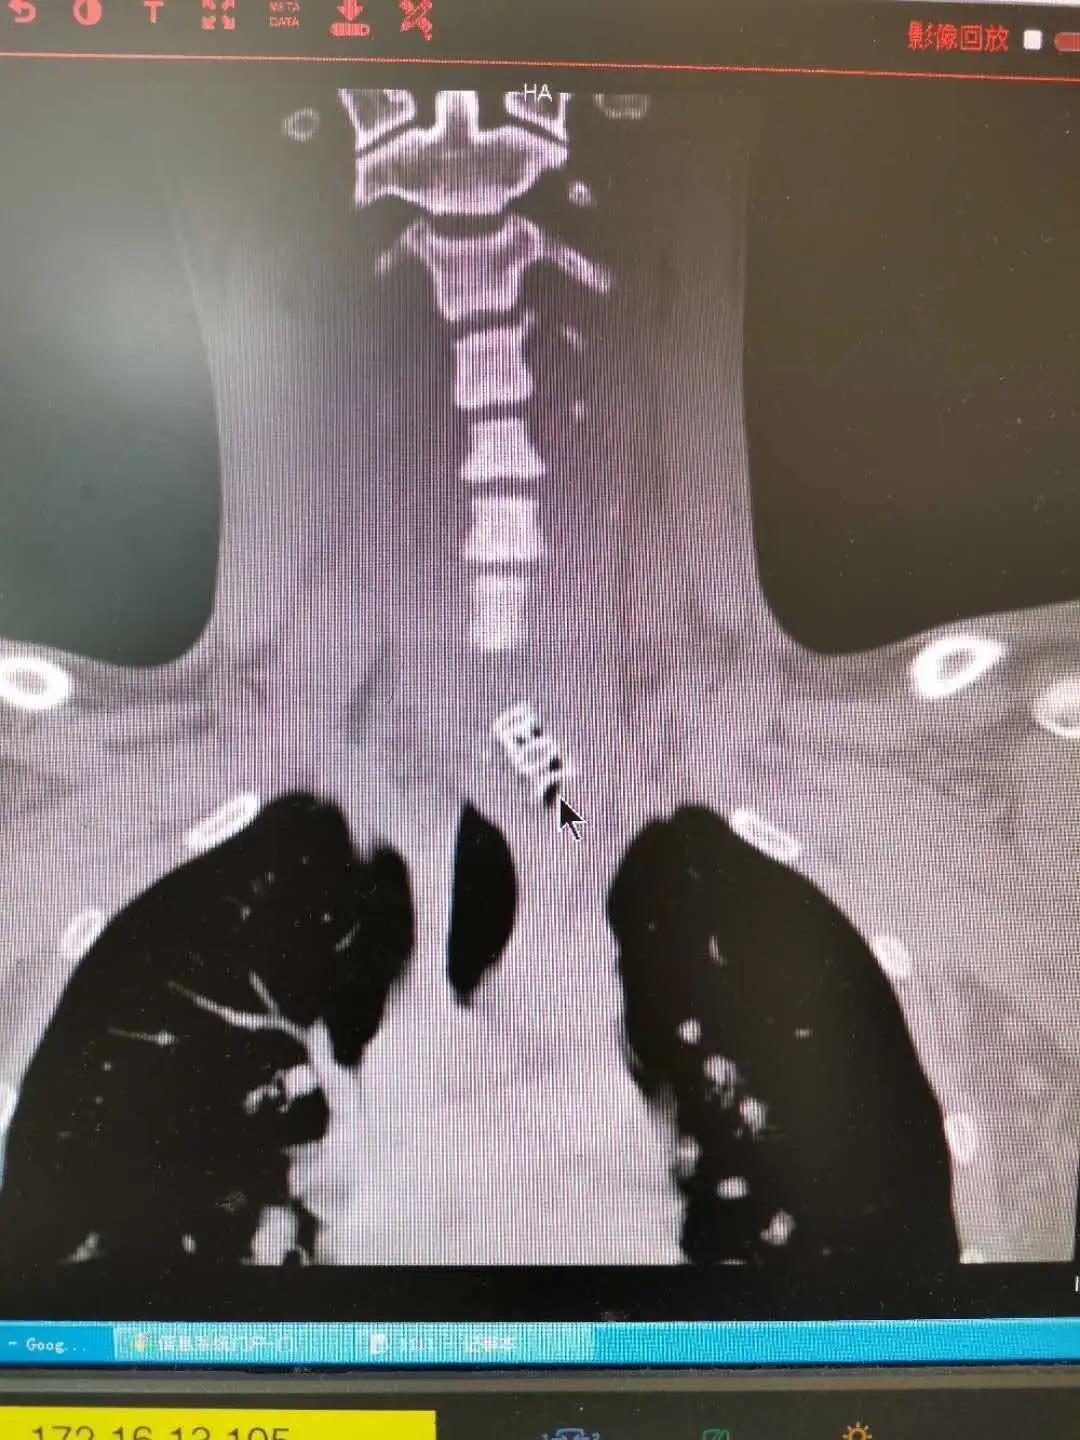

该院耳鼻喉科接诊医生仔细询问病史后怀疑为食管异物,食道CT提示在食管上段处有异物。第二天,小杨被收入耳鼻喉科的住院部,当天下午便接受了食道镜手术治疗。从食道镜检查到内镜取异物,整个过程仅用了10分钟,其中取异物用时仅1分钟,术中没有出血。